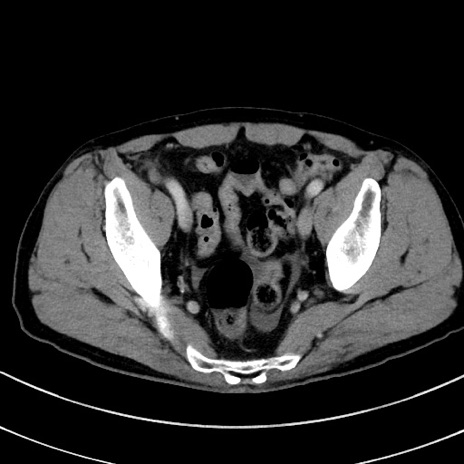

症例8(横断像)

【症例】 60歳代男性

【主訴】 黒色吐物

【現病歴】 4日前から嘔気自覚、2日前の朝食後にも嘔気あり、自分で手で嘔吐反射起こし嘔吐したところ血が混ざっていたため受診。

【既往歴】 5年前汎発性腹膜炎を伴う急性虫垂炎で手術、高血圧、前立腺肥大症、高脂血症

【身体所見】 腹部正中に手術癩痕あり 腹部平坦・軟圧痛なし膨満感あり

【データ】WBC 8400、CRP 4.54